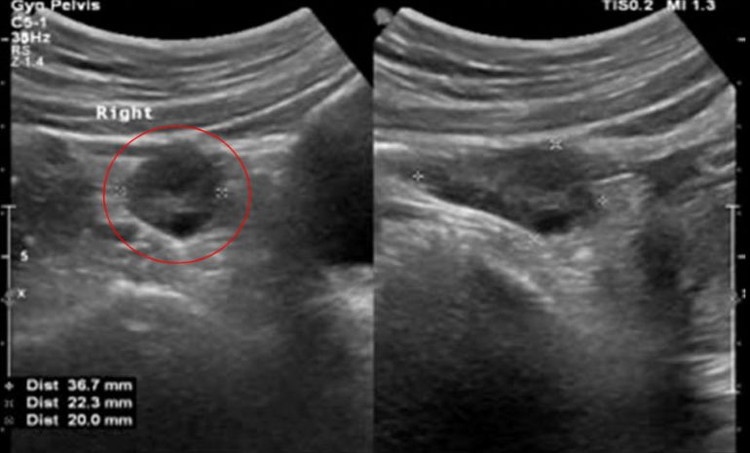

Theo BS.CKI Nguyễn Thanh Sơn Vũ, chuyên khoa Ngoại Nhi, Bệnh viện Đa khoa Tâm Anh TP HCM thông tin bệnh nhi có khối u kích thước 42x45x70mm.

| Kết quả siêu âm phát hiện khối u trong buồng trứng bệnh nhi. Ảnh BVCC |

Trường hợp bé Trang, khối u có kích thước trên 40mm là dạng nang buồng trứng thực thể. Nguyên nhân gây bệnh là do các tổn thương xuất phát từ mô buồng trứng tiến triển thành u. Những bé gái trong độ tuổi vị thành niên sẽ dễ bị nhầm tưởng đau bụng kinh, rối loạn kinh nguyệt… Trẻ nhỏ hơn thường được phát hiện bệnh tình cờ khi đi khám sức khỏe hoặc khám bệnh tiêu hóa với các triệu chứng như đau bụng, sờ thấy sưng, táo bón, rối loạn tiểu tiện…